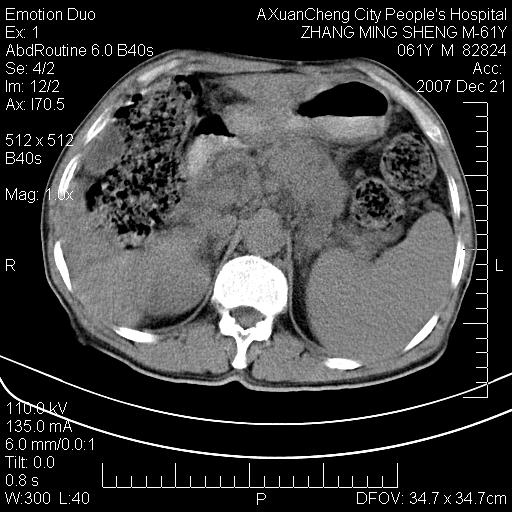

标题: CT11031:M61Y,胰腺占位 [打印本页]

标题: CT11031:M61Y,胰腺占位

大家侃侃门静脉和胆管系统怎么回事,肝内转移?

胰腺癌肝转移

肝硬化,门脉高压,脾肿大;弥漫性肝癌,肝内、门脉、腹膜后淋巴结转移,肝内外胆管扩张,胰头区占位,建议mr检查

胰腺癌伴肝内转移;门脉、肠系膜上v癌栓形成。

考虑为:胰腺癌伴肝脏转移、腹膜后淋巴结转移,门静脉及肠系膜上静脉瘤栓形成。

胰体尾癌伴肝内转移,门静脉及肠系膜上静脉瘤栓形成.

肝硬化,脾大. 胰腺癌伴肝内转移;门脉、肠系膜上v癌栓形成。